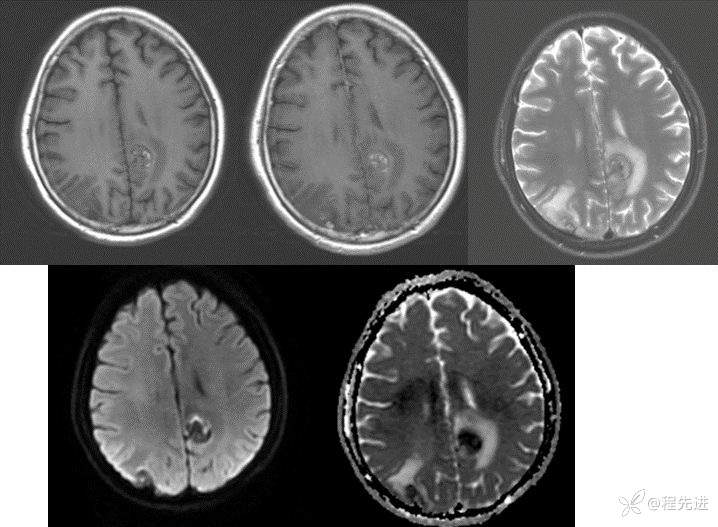

MRI:

img